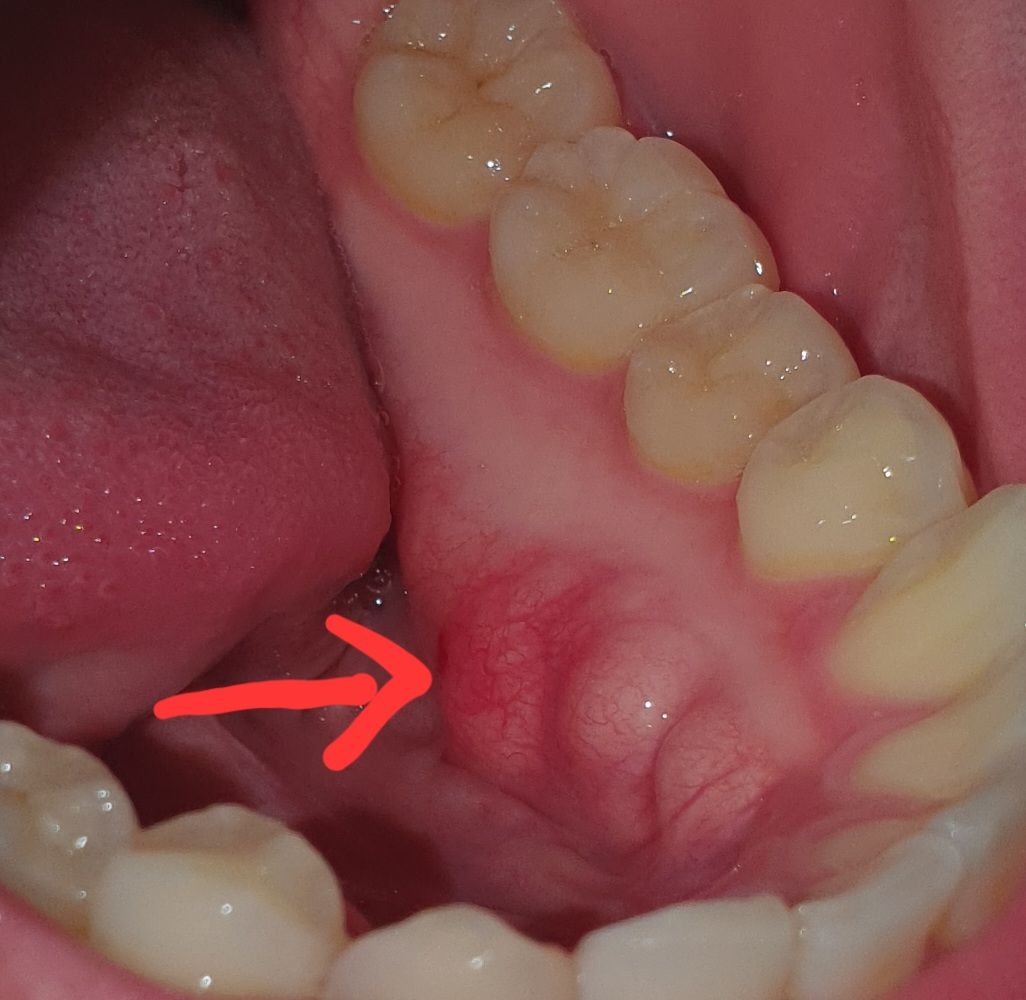

입안에 딱딱하고 볼록한게 뭘까요?

양쪽에 다 있는데 딱딱하고 볼록해요

말씀하신 것은 정상적인 조직인 치과 용어로는 골융기(torus)일 가능성이 큽니다. 이는 비정상적인 치조골 성장으로 나타나지만 이는 특별히 치료의 대상은 아닙니다. 물론 추후에 틀니 등을 할 때는 해당 부위를 제거해주어야 하지만 그렇지 않은 경우에는 지금 상태에서 불편감이 없다면 치료하지 않아도 됩니다.

해당부위는 뼈가 밖으로 자라나온 외골증이라고 합니다.

하악 내부쪽으로 잘 생기기 때문에 문제를 발생시키지 않기 때문에 크게 걱정하지 않으셔도 됩니다.

해당부위를 자극했을 경우 잇몸이 매우 얇기 때문에 상처가 생길수 있어요.

사진으로 보기에는 외골증인 것으로 보입니다. 외골증은 보통 치료를 필요로 하지 않습니다.

다만 너무 불편하거나 혀쪽으로 닿아서 불편한경우 구강외과에서 제거하는 치료를 받아볼 수 있습니다. 감사합니다.